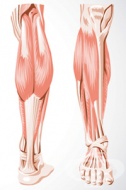

S86 Травма на мускулите и сухожилията на ниво подбедрица

Мускули и сухожилия на ниво подбедрица са класифицирани в три групи: - Задна мускулна група е състав...

S86.1 Травма на друг(-и) мускул(-и) и сухожилие(-я) от задната мускулна група на ниво подбедрица

Мускулите от задната мускулна група се нареждат в два слоя: Повърхностна група - m.triceps sure и m....

S86.2 Травма на мускул(-и) и сухожилие(-я) от предната мускулна група на ниво подбедрица

Мускулите от предната мускулна група са: m.tibialis anterior, m.extensor hallucis longus, m.extensor...